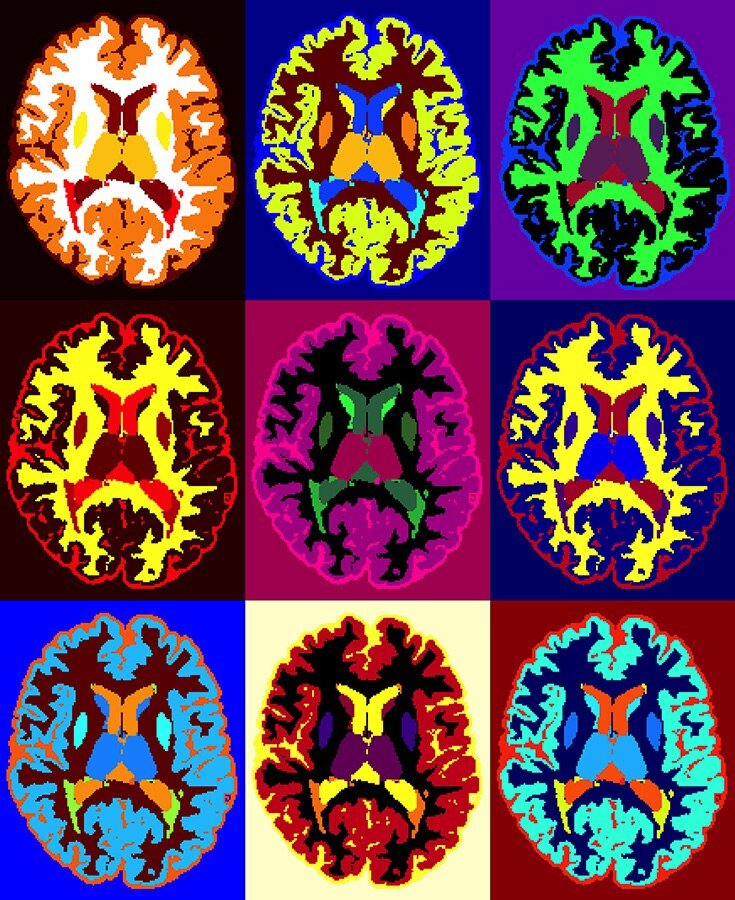

МРТ рассеянного склероза в стиле Энди Уорхола

Credit: Ilena George and Daniel Reich, National Institute of Neurological Disorders and Stroke, National Institutes of Health Перед вами — не картина Энди Уорхола, хотя изображение и стилизовано под нее. Это картинка из Flickr Национальных институтов здоровья США, где изображено аксиальное МРТ мозга с рассеянным склерозом. Разные цвета соответствуют разным типам тканей. А дальше — фантазия авторов и стиль Энди Уорхола.